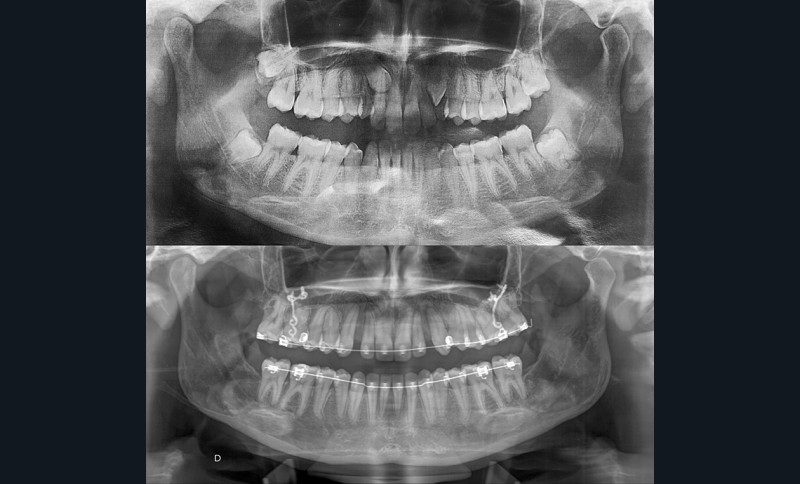

Aline se présente à la consultation pour une demande esthétique concernant ses deux canines lactéales qu’elle trouve trop petites et trop blanches (fig. 1a). Elle présente une classe II squelettique légère sur un schéma méso-divergent. D’un point de vue dentaire, une supraclusion est associée à une classe II d’Angle complète à gauche et de 4 mm à droite. Les canines maxillaires sont incluses (une vestibulaire et une palatine), avec persistance de leurs dents lactéales sur l’arcade (fig. 1b-h).

Dans un premier temps, des attaches bidimensionnelles (20/25 antérieures et 22/28 postérieures en Roth) sont collées aux deux arcades. L’alignement-nivellement est initié par des 0.014 Niti. Des plaques d’ancrages osseuses…